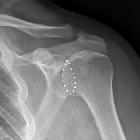

Loss of half-moon overlap sign, which does not really roll off the tongue, is a sign of posterior shoulder dislocation on AP radiographs.

On a normal true anteroposterior image, there is a half-moon overlap between the humeral head and the glenoid. In a posteriorly dislocated shoulder, there is lateral displacement of the humeral head with respect to the glenoid (losing the half-moon overlap).